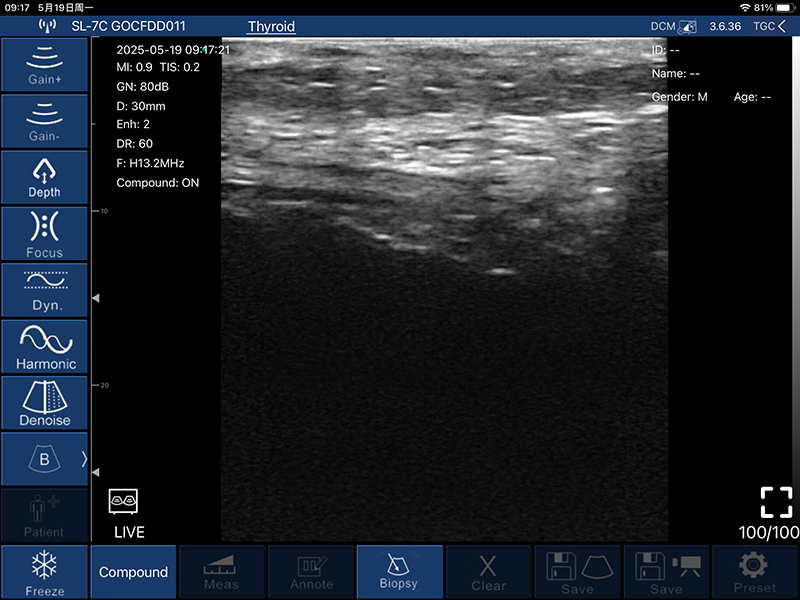

• 扫描深度:20/30/40/60mm,可调

• B模式

增益:30db-105db

降噪:0-1-2-3-4

动态范围: 40-50-60-70-80-90-100-110

• 图像调节:增益、焦点、

反相脉冲谐波、降噪